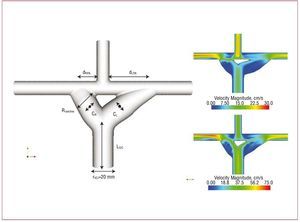

To further refine the design of the Y-graft for the Fontan procedure, the Y-graft design was optimized using an idealized model employing the methods outlined in Marsden et al.37 An automated code was developed to define the Y-graft geometry with 6 design variables and produce a 3D model for each design (Figure 5). The results demonstrate that the optimal Y-graft geometry changes significantly from rest to exercise conditions, with larger radius branches and a wider angle at rest compared to exercise. The results have also demonstrated a trade-off between energy efficiency (larger graft branches) and areas of lower WSS (smaller graft branches) using competing design objectives. Further investigation is needed to establish a link between WSS and thrombus formation.

Figure 5. An idealized model of the Fontan Y-graft parameterized with 6 design variables (Rbranches, dRPA, dLPA, CR, CL and LIVC) for automated design optimization. Optimal designs are shown at rest (upper right) and exercise (lower right). CR and CL indicates branch curvature; dRPA and dLPA, distances from superior vena cava to branch anastomoses; LIVC, length of inferior vena cava; Rbranches, graft branch radius.